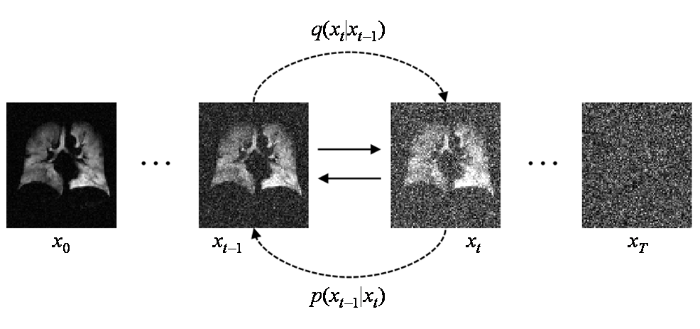

图2

前向扩散逐步添加高斯噪声与逆向扩散逐步去除噪声恢复图像过程

Fig. 2

Forward diffusion progressive addition of gaussian noise and backward diffusion progressive removal of noise recovery image processes

模型的前向扩散加噪过程可以看作是将上一时刻输入的图像与一个高斯分布采样进行加权融合,如(2)式和(3)式所示,N表示高斯分布,I是单位矩阵,

其中,

逆向去噪过程仍然是一个逐步进行的过程,它可以利用贝叶斯公式进行推导[24].如果我们的目标是从目标数据分布

其中,μ 表示噪声均值.在扩散模型中利用神经网络来拟合出噪声预测模型,得到均值

由于方差由扩散过程的参数决定,通常是固定的,所以无需通过神经网络拟合,而参数